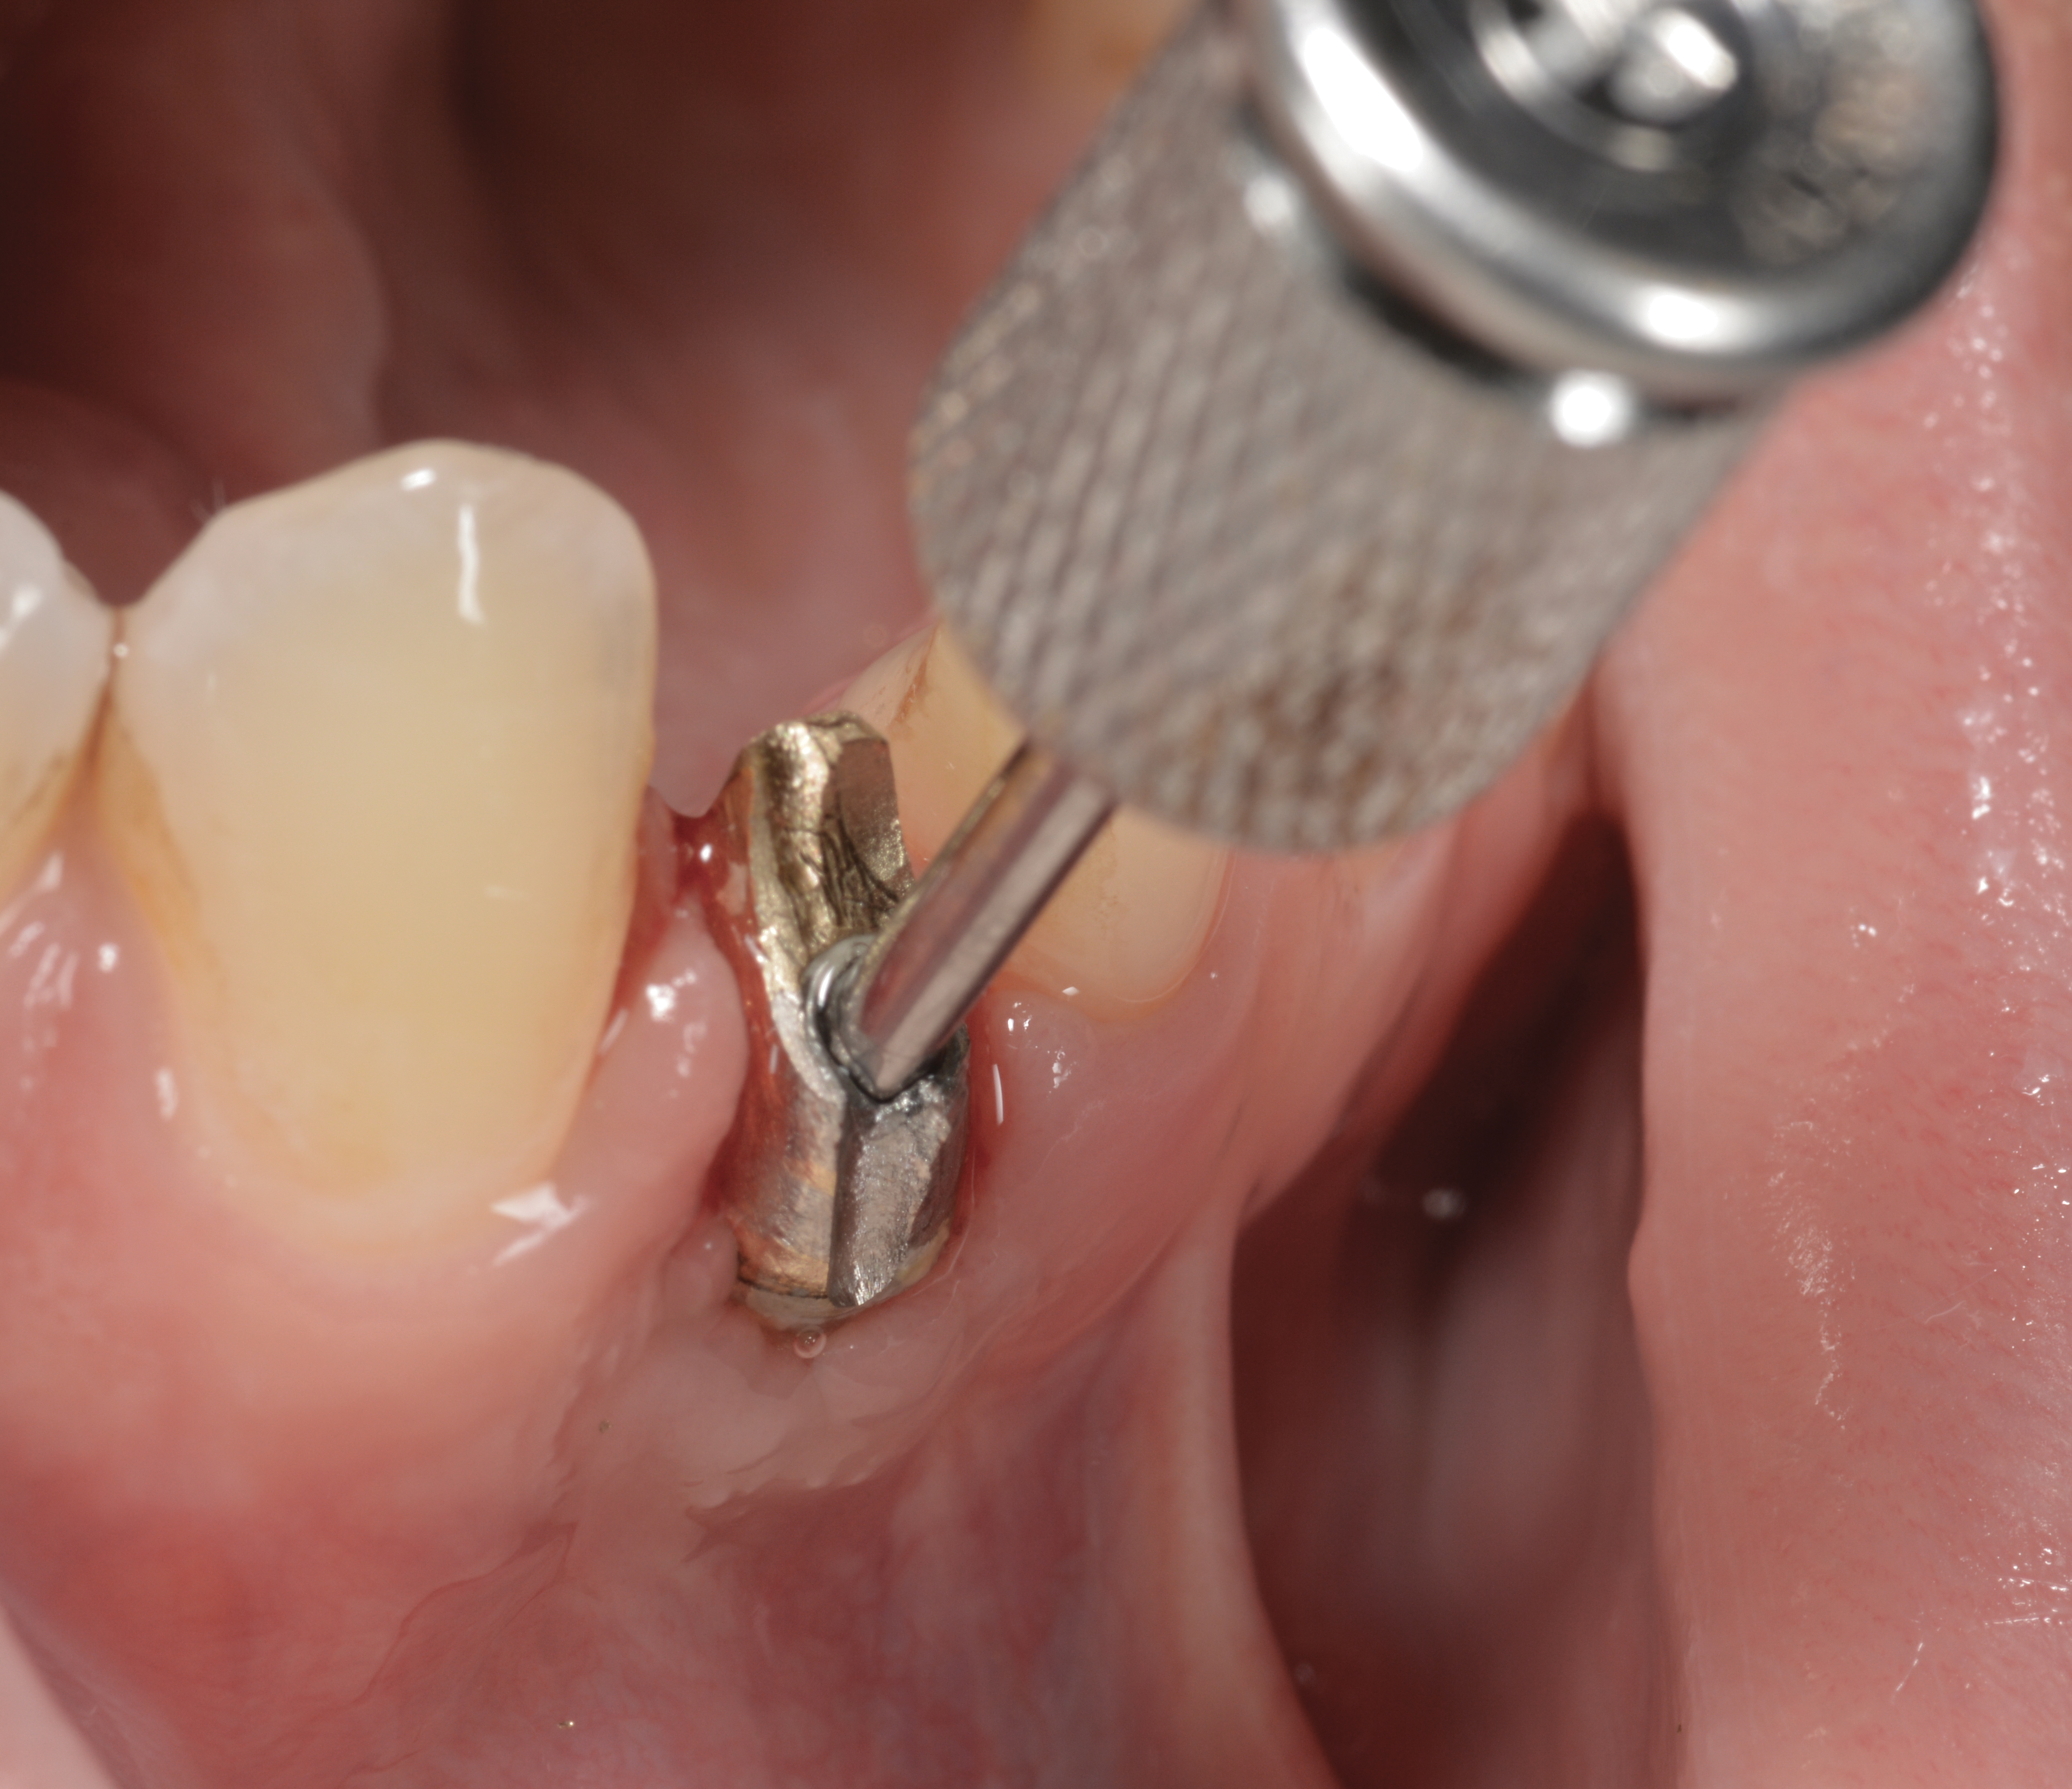

The following case report provides an example of this case scenario: A 24-year-old white male presented with congenitally missing tooth No. 26 restored with a single-tooth cement-retained implant restoration. The implant was placed excessively to the facial aspect of the edentulous site and too shallow, and the periodontal phenotype was thin scalloped (Figure 32). In an effort to mimic the lost midfacial soft tissues, pink ceramics were used as a cosmetic facade. Even though the restoration was not in the esthetic zone, the patient was highly displeased with the esthetic outcome and sought remediation.

The crown and screw-retained custom abutment were removed, and a surgical cover screw was placed into the implant, thereby allowing spontaneous gingival augmentation in situ (Figure 33 and Figure 34). Note that the lingual aspect of the implant site was significantly more coronal than the labial aspect, which was positive because the defect would be limited to a facial–lingual defect. A fixed RBR bridge was cemented on the adjacent teeth and used as a tooth-supported transitional provisional restoration (Figure 35). A few weeks were allotted to let the soft tissue heal and migrate around the cover screw (Figure 36) to see if there would be complete coverage, thereby allowing a soft-tissue augmentation procedure to be performed with primary flap closure as in clinical scenario No. 2. The major obstacle in achieving a positive tissue response was that the implant depth was also deficient because the implant–abutment connection was at the level of the free gingival margin. It was decided that the best treatment option would be to remove the implant. A high-powered reverse-torque device (Fixture Remover Kit, NeoBiotech, www.neobiotechus.com) was used to remove the implant atraumatically (Figure 38 through Figure 41). The implant socket was allowed to heal for several months not unlike an extracted tooth (Figure 42). A new implant was placed in a better position from both a restorative and esthetic perspective (Figure 43), and after a few months of healing, a new crown was made (Figure 44). A satisfactory functional and esthetic result was achieved (Figure 45 and Figure 46) without employing pink porcelain.

Fig 33. Excessive facial angulation of the implant placement shown with an abutment driver in the access screw hole.

Figure 33

Fig 34. A surgical cover screw was placed in an attempt to decoronate the implant and gain soft-tissue coverage in situ.

Figure 34

Fig 36. Two weeks after RBR placement, the soft tissue did not adequately cover the implant. The problem was in poor implant angulation and proper depth to allow the soft tissues to cover over.

Fig 37. The reverse-torque driver can put up to 450 Ncm of force to disrupt osseointegration.

Figure 37

Fig 38. A reverse-torque screw was placed into the implant.

Figure 38

Fig 39. A counter-torque device was placed over the reverse-torque screw.

Figure 39

Fig 40. The implant was easily unscrewed within minutes in a minimally invasive manner with less trauma to the surgical site.